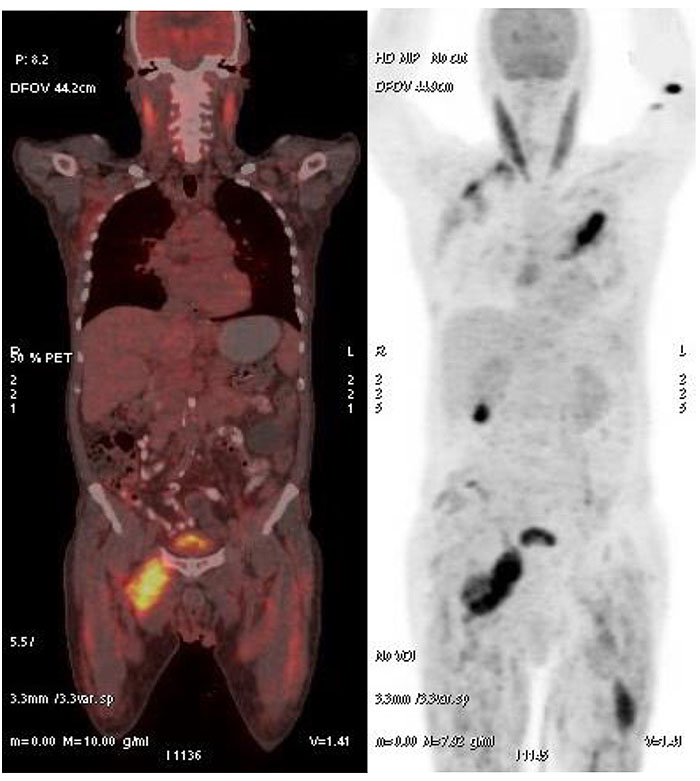

Biopsy and histopathology of the left breast lump revealed a circumscribed nodule of lymphoid cells, prominence of cells with vesicular chromatin & conspicuous nucleoli, lymphoid cells observed to be infiltrating the surrounding skeletal muscle fibres. The cells were CD20 positive; CD3, CD5, CD10, CD23 negative; Ki-67 labelling index 80% on immunohistochemistry, suggesting a diagnosis of Non Hodgkin’s Lymphoma, Diffuse Large B cell Type. A Positron Emission Tomography–Computed Tomography (PET-CT) Fig. (2). was done which revealed an increased Fludeoxyglucose (FDG) avidity in the right adductor compartment (Standardized uptake value SUV 10.3), right gluteal muscles (SUV 5.3), right parascapular muscles (SUV 7.2), left pectoralis major muscle (10.1), and left thigh muscles (7.9), suggestive of neoplastic etiology.

Fig. (2). PET-CT Images revealing high FDG Avidity in multiple skeletal muscles.

Though imaging is the frequent initial step for the evaluation of such patients, the radiological features of skeletal muscle lymphoma are non-specific and cannot differentiate lymphoma from other conditions, such as myositis, trauma, sarcoma or metastasis. The diagnosis requires a skeletal muscle biopsy and histopathological examination. PET-CT has a significant role not only as a diagnostic modality, but also for staging and subsequently, for monitoring of therapeutic response [6].

Our patient had breast involvement as evidenced by the biopsy findings of the breast lump and multiple skeletal muscle involvement as evidenced by the PET-CT findings. A separate skeletal muscle biopsy was not considered since evidence provided by the breast biopsy and PET-CT was highly suggestive of the diagnosis.